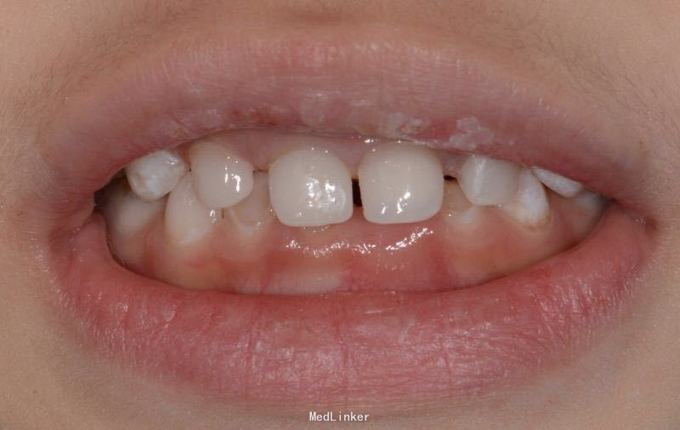

A1 B1残根,根尖炎。 常规根管治疗,树脂充填,抛光 A2 B2残根,常规去腐,备洞,树脂充填,抛光

乳牙功能恢复对发音,面部肌肉骨骼生长,儿童自信心的增长都有帮助